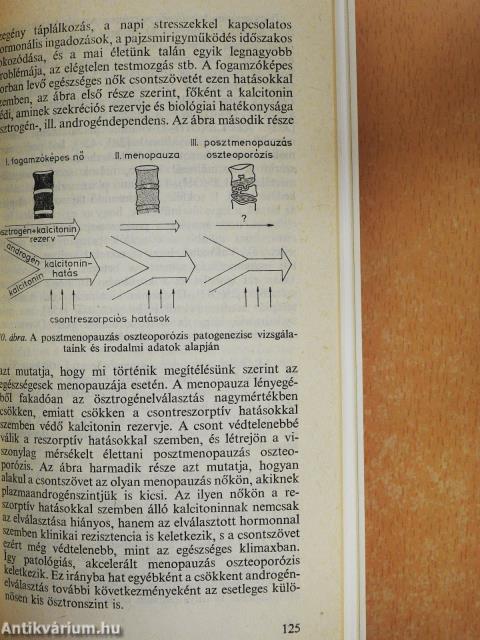

| Oszteoporózisok | 111 |

| Általános kórszármazás | 111 |

| Primer oszteoporózisok | 117 |

| Involúciós oszteoporózisok | 117 |